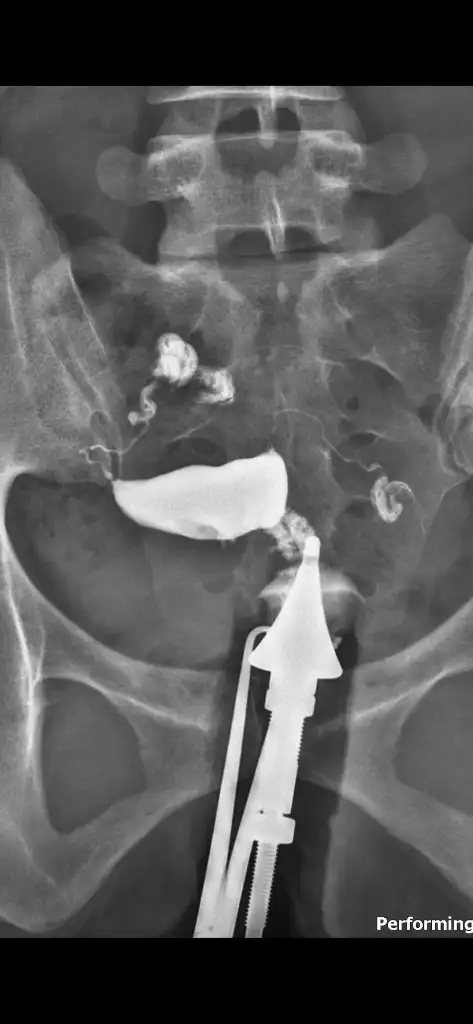

Ultrasonda görmediler rahim filmi çekildi orda fark edildiRahimdeki perdeyi doktor nasıl gördü acaba ultrasonda görünüyor mu

Rahim filmi çektirdim raporunu almak için gitmem gerekiyor e nabıza yüklemediler. Raporda ne yazıyor bilmiyorum hiç. Zeynep kamilde de iyi bir doktora denk gelemedim tüm detayları sorayım.Bnm Zeynep kamilde 3 boyutlu bir ultrason cihaziyla rahimde perde olduğunu tespit etmislerdi